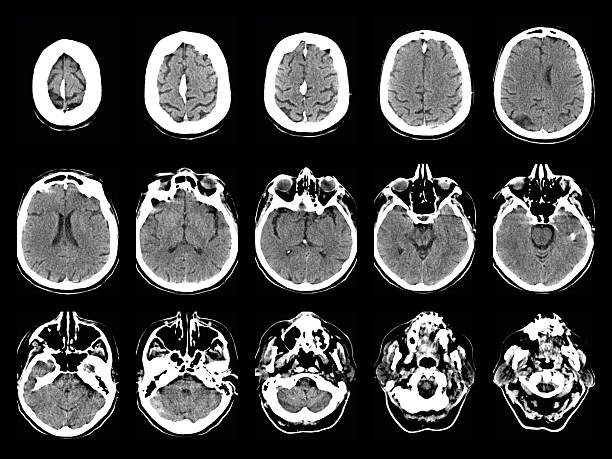

神經系統疾病,也稱為神經系統疾病或病癥,是影響中樞神經系統(大腦和脊髓)、周圍神經系統(大腦和脊髓以外的神經)或兩者的疾病。這些疾病是由神經系統的結構、功能或化學異?;蚬δ苷系K引起的。

神經系統疾病有多種病因,包括遺傳因素、發育問題、感染、免疫系統疾病、退化過程、腫瘤、創傷和其他潛在健康狀況。它們會影響任何年齡段的人,從出生到老年。

神經系統問題會嚴重影響老年人的生活質量。阿爾茨海默病、帕金森病和癡呆癥等疾病會導致認知能力下降、記憶力喪失、功能障礙以及日?;顒右蕾囁?。有效管理這些疾病對于老年人保持獨立和幸福至關重要。